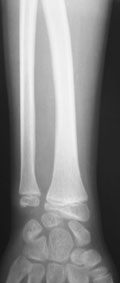

Лучевая косорукость

11-летний любитель лазить по деревьям 7 месяцев назад получил открытый дистальный остеоэпифизеолиз левого луча. ПХО была сделана с трудом; о репозиции, со слов, и не помышляли. Неделю назад удалось открыто адаптировать костные фрагменты, фиксировать аппаратом. Сразу сделали кортикотомию в/3 луча. Начали его удлинение. Вопрос: учитывая отсутствие дистальной зоны роста стоит ли "переудлинить" луч? Если да, то на какую величину?

как видно из Р снимков, дистальная ростковая зона повреждена. делать эпифизеодез думаю что не целесообразно. лучелоктевая косорукость преопределена, поэтому востановление придеться делать в несколько этапов. величину гиперкоррекции предусмотреть трудно не зная темпов роста, думаю что впределах 5-10мм. С уважекнием Владимир Старостенко. купянск .Харьковской. Украина

Глядя на предложенные снимки, сразу же возникает вопрос о необходимости открытого сопоставления отломков лучевой кости. Мне кажется, репозицию возможно было бы сделать и ваппарате Илизарова с использованием смещенных шарниров и этапной дистракции без выполнения разреза. Росковый хрящ, скорее всего, большей частью погиб. Но в аппарате Вы могли срепонировать и стабилизировать отломки, восстановить на время соотношение лучевой и локтевой костей в лучезапястном суставе, пусть даже дозированной осевой дистракцией.

Маленькое замечание: кортикотомия произведена (кажется так по снимку) в невыгодном с точки зрения кровоснабжения кости месте. Дитракция в аппарате приведет к сдавлению не растянутого в аппарате лучезапястного и межзапястного суставов (спица за пястные кости не проведена).

Проведена. Иначе как бы фрагменты удерживались? Через дистальный фрагмент луча спицу предполагаю провести в конце периода дистракции. Если пациента за праздники не увезут обратно в Херсон - есть и такая вероятность. Еще раз благодарю всех.